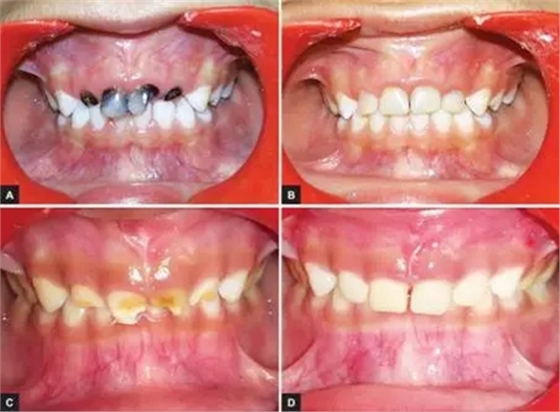

本研究中,其他患齲齒或牙外傷的患兒均采用此方法使用臨時(shí)冠材料進(jìn)行美學(xué)修復(fù),下圖分別為兩例乳前牙齲齒(圖2)和兩例牙外傷(圖3)的病例。

圖2.(2-A,2-B為乳前牙齲齒病例1 2-C,2-D為乳前牙齲齒病例2)